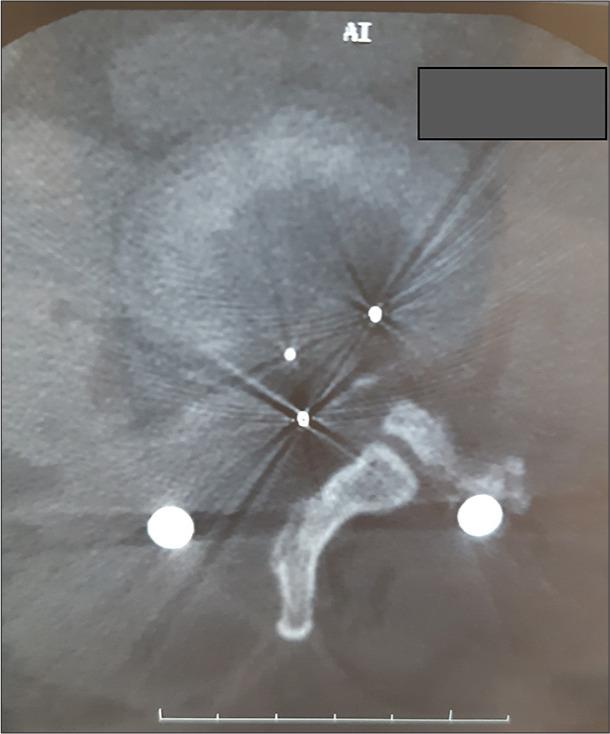

A 46-year-old female underwent a TLIF L3-L4. Five months later, she presented with cauda symptoms/signs of dorsal cage migration that warranted surgical removal.

一名46岁女性接受了L3-L4节段的TLIF手术。五个月后,她出现了融合器向后移位至椎管的马尾症状/体征,需要进行手术取出。